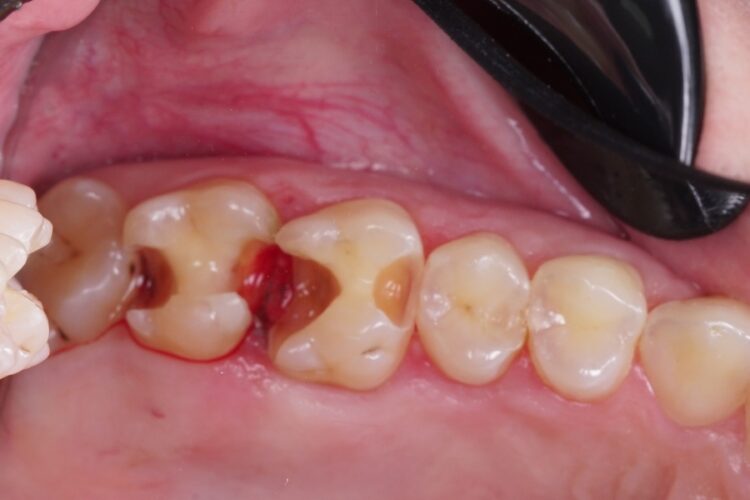

Пломбування жувальних зубів фотополімером

Пацієнт звернувся зі скаргою на постійне застрягання їжі між бічними зубами, та неприємний запах при чищенні зубною ниткою між ними. Було діагностовано неякісне прилягання старих пломб та вторинний карієс, що розвинувся під ними. Ми провели очищення зубів від старого матеріалу та каріозного ураження. Пломбування зубів проведено матеріалом ASTERIA, Tokuyama (Японія) з формуванням якісного та щільного контакту між ними.